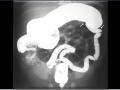

Intubação seletiva em recém-nascido

Dez de 2015.